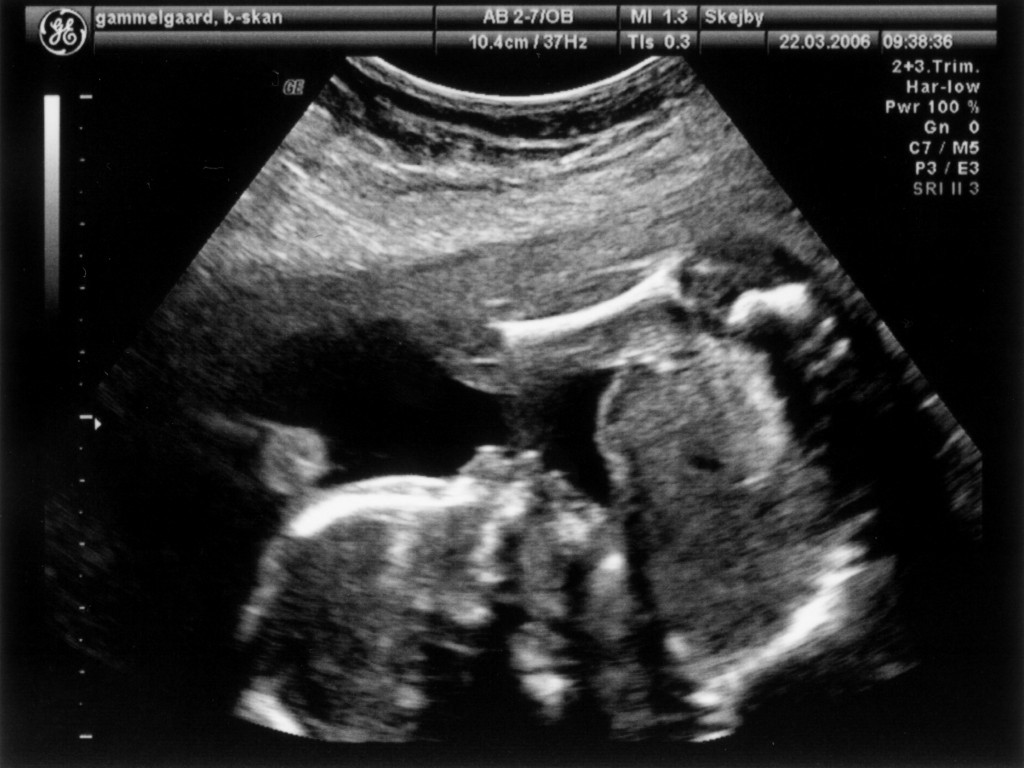

Ultralydsskanning den 22. marts 2006

Vi har så endelig været på Skejby Sygehus, hvor specialisterne skulle vurdere babys hjerte. Konklussionen var at baby og hendes hjerte ikke fejler noget - alt er i den skønneste orden. Der blev foretaget en meget grundig skanning og billederne blev vurderet af en afdelingslæge, en overlæge samt en overlæge med mange års international erfaring i børns hjertefejl. Det var en stor lettelse at hun ikke fejler noget. Baby blev undersøgt generelt en gang til at specialisterne og alt er som det skal være. De kunne desuden konstatere, at det er en pige... Du kan se de billeder vi fik fra skanningen herunder.

Baby ligger med hovedet nederst i midten og kigger op. Hun flekser så meget i ryggen at hendes ben går helt op over hovedet. Babys hjerte med nogle målinger.